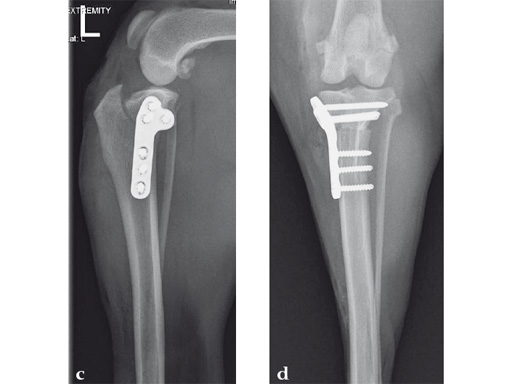

An 11-year-old female, spayed, 13.6 kg cocker spaniel had a complete tear of the left cranial cruciate ligament. A 2.4 mm TPLO plate was perfect for this dog due to the excessive slope of the tibial plateau (30) and the size of the dog. Three 2.4 mm locking screws were used proximally and three 2.4 mm cortical screws were used distally. The contour of this plate matches the contour of the bone almost perfectly. The plate is also designed to optimize the angle of the proximal screws so that they engage the most dense and thickest bone and avoids penetration of the stifle joint.

A 10-year-old female, spayed, 6.0 kg cat had a partial tear of the left cranial cruciate ligament, meniscal mineralization, and a medial meniscal tear. The cat was treated with a partial meniscectomy and TPLO . A 2.0 mm TPLO plate was perfect for this cat due to the slope of the tibial plateau (25) and the size of the cat. Three 2.0 mm locking screws were used proximally and three 2.0 mm cortex screws were used distally. The contour of this plate does not perfectly match the contour of the proximal tibia, but use of locking screws in this segment avoids any potential angulation of the segments as the screws are tightened. The cat healed uneventfully and returned to normal function.